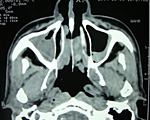

写真:慢性副鼻腔炎の方の画像

慢性副鼻腔炎の方の画像

鼻の穴の周辺には副鼻腔(ふくびくう)と呼ばれるいくつかの空洞があります。これらの空洞は鼻の穴とつながっているのですが、こちらの空洞に慢性的にウミや粘膜が溜まってしまう病気がちくのう症(慢性副鼻腔炎)です。症状として、頭が重い、ドロっとした鼻が出る、鼻がつまるなどが挙げられます。当院での治療法としては抗生剤の少量長期の投与と通院による処置の組み合わせによる治療が原則ですが、症状や患者さんのご希望に応じ、内視鏡を用いた手術を行う場合があります。

レントゲンの撮影によって、副鼻腔炎の状況の診断が可能です。鼻の周辺のレントゲンを撮ると副鼻腔は本来空洞のために、黒く写りますが、副鼻腔炎の症状が発症し、ウミが溜まっているとその部分が白くうつります。